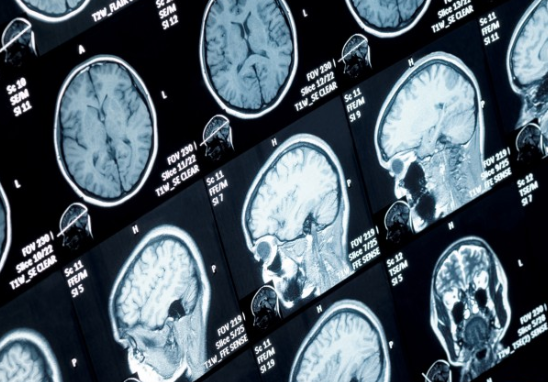

신경계에 생기는 신경질환의 한 종류인 삼차 신경병증(신경통)을 알기 위해서는 삼차신경이라는 용어를 알아야 하는데요. 삼차신경이란 얼굴, 머리등에 온도나 통증을 느끼는 감각을 뇌에 전달해 주는 뇌신경의 일종이라 생각하시면 됩니다. 이러한 뇌신경에 이상이 생겨서 얼굴감각에 이상이 생긴다거나 잘 못씹는 경우가 생기면 삼차신경병증이라고 부르고 통증이 생기면 삼차 신경통이라고 부르게 됩니다.

앞서 말한 중이염 / 치주 감염 / 부비동 질환 / 급성 녹내장 / 대상포진등 다양한 원인으로 인해 신경학적인 검사를 하게 되는데 지속적인 신경통증이 나타나는 것이 아니라 통증이 지속되다가 사라지기 때문에 두경부 검사를 해서 신경학적으로 이상이 없는데도 특정 부위나 얼굴 한쪽등에 통증이 지속적으로 나타난다면 삼차 신경통으로 생각한다고 합니다.